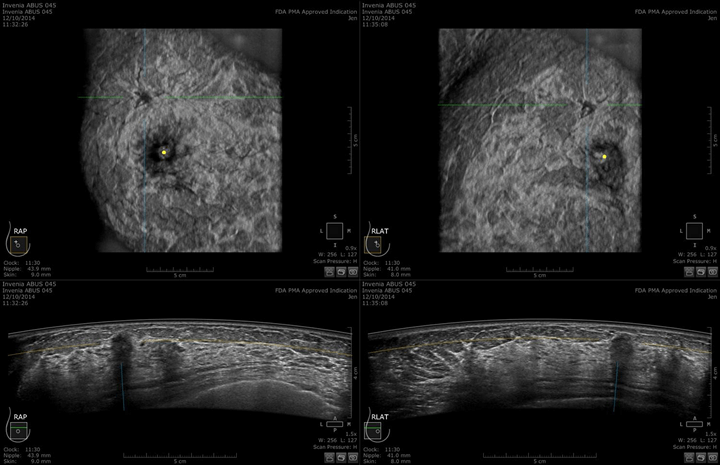

東京美容外科では当院手術だけでなく他院手術後の方も痛みが少なく受けられる乳がん検査専用の超音波検査装置『エイバス』を美容クリニックで初めて導入しました。

■インベニアエイバスとは

痛みやストレスを少なくして検査が受けられる、乳がん検査専用の超音波検査装置です。

検査方法は、スキャンヘッドを片方の乳房全体に当てて撮影するだけで済みます。従来の超音波検査よりも短時間で終わり、マンモグラフィ検査よりも痛みを伴いにくいことが特徴です。まだ保険対象外となるため、受診費用は自費となります。(1回 33,000円(税込))